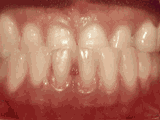

牙列拥挤,牙槽骨过窄,牙齿没有足够空间,只好前后左右高低上下乱长,经过矫正后的牙齿是这样的~